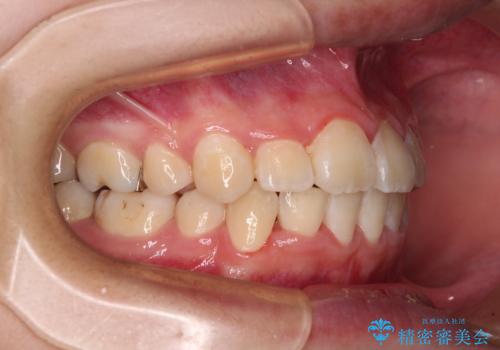

- 上下の八重歯と前歯のデコボコを気にして来院された患者様です。

右上の八重歯が特に著しく、上顎正中が右側にシフトしていました。

正中位置の改善に時間がかかることが予想され、2年半を治療期間の目標としておりましたが、20歳と年齢が若いこともあり、2年2ヶ月で治療を終えることができました。